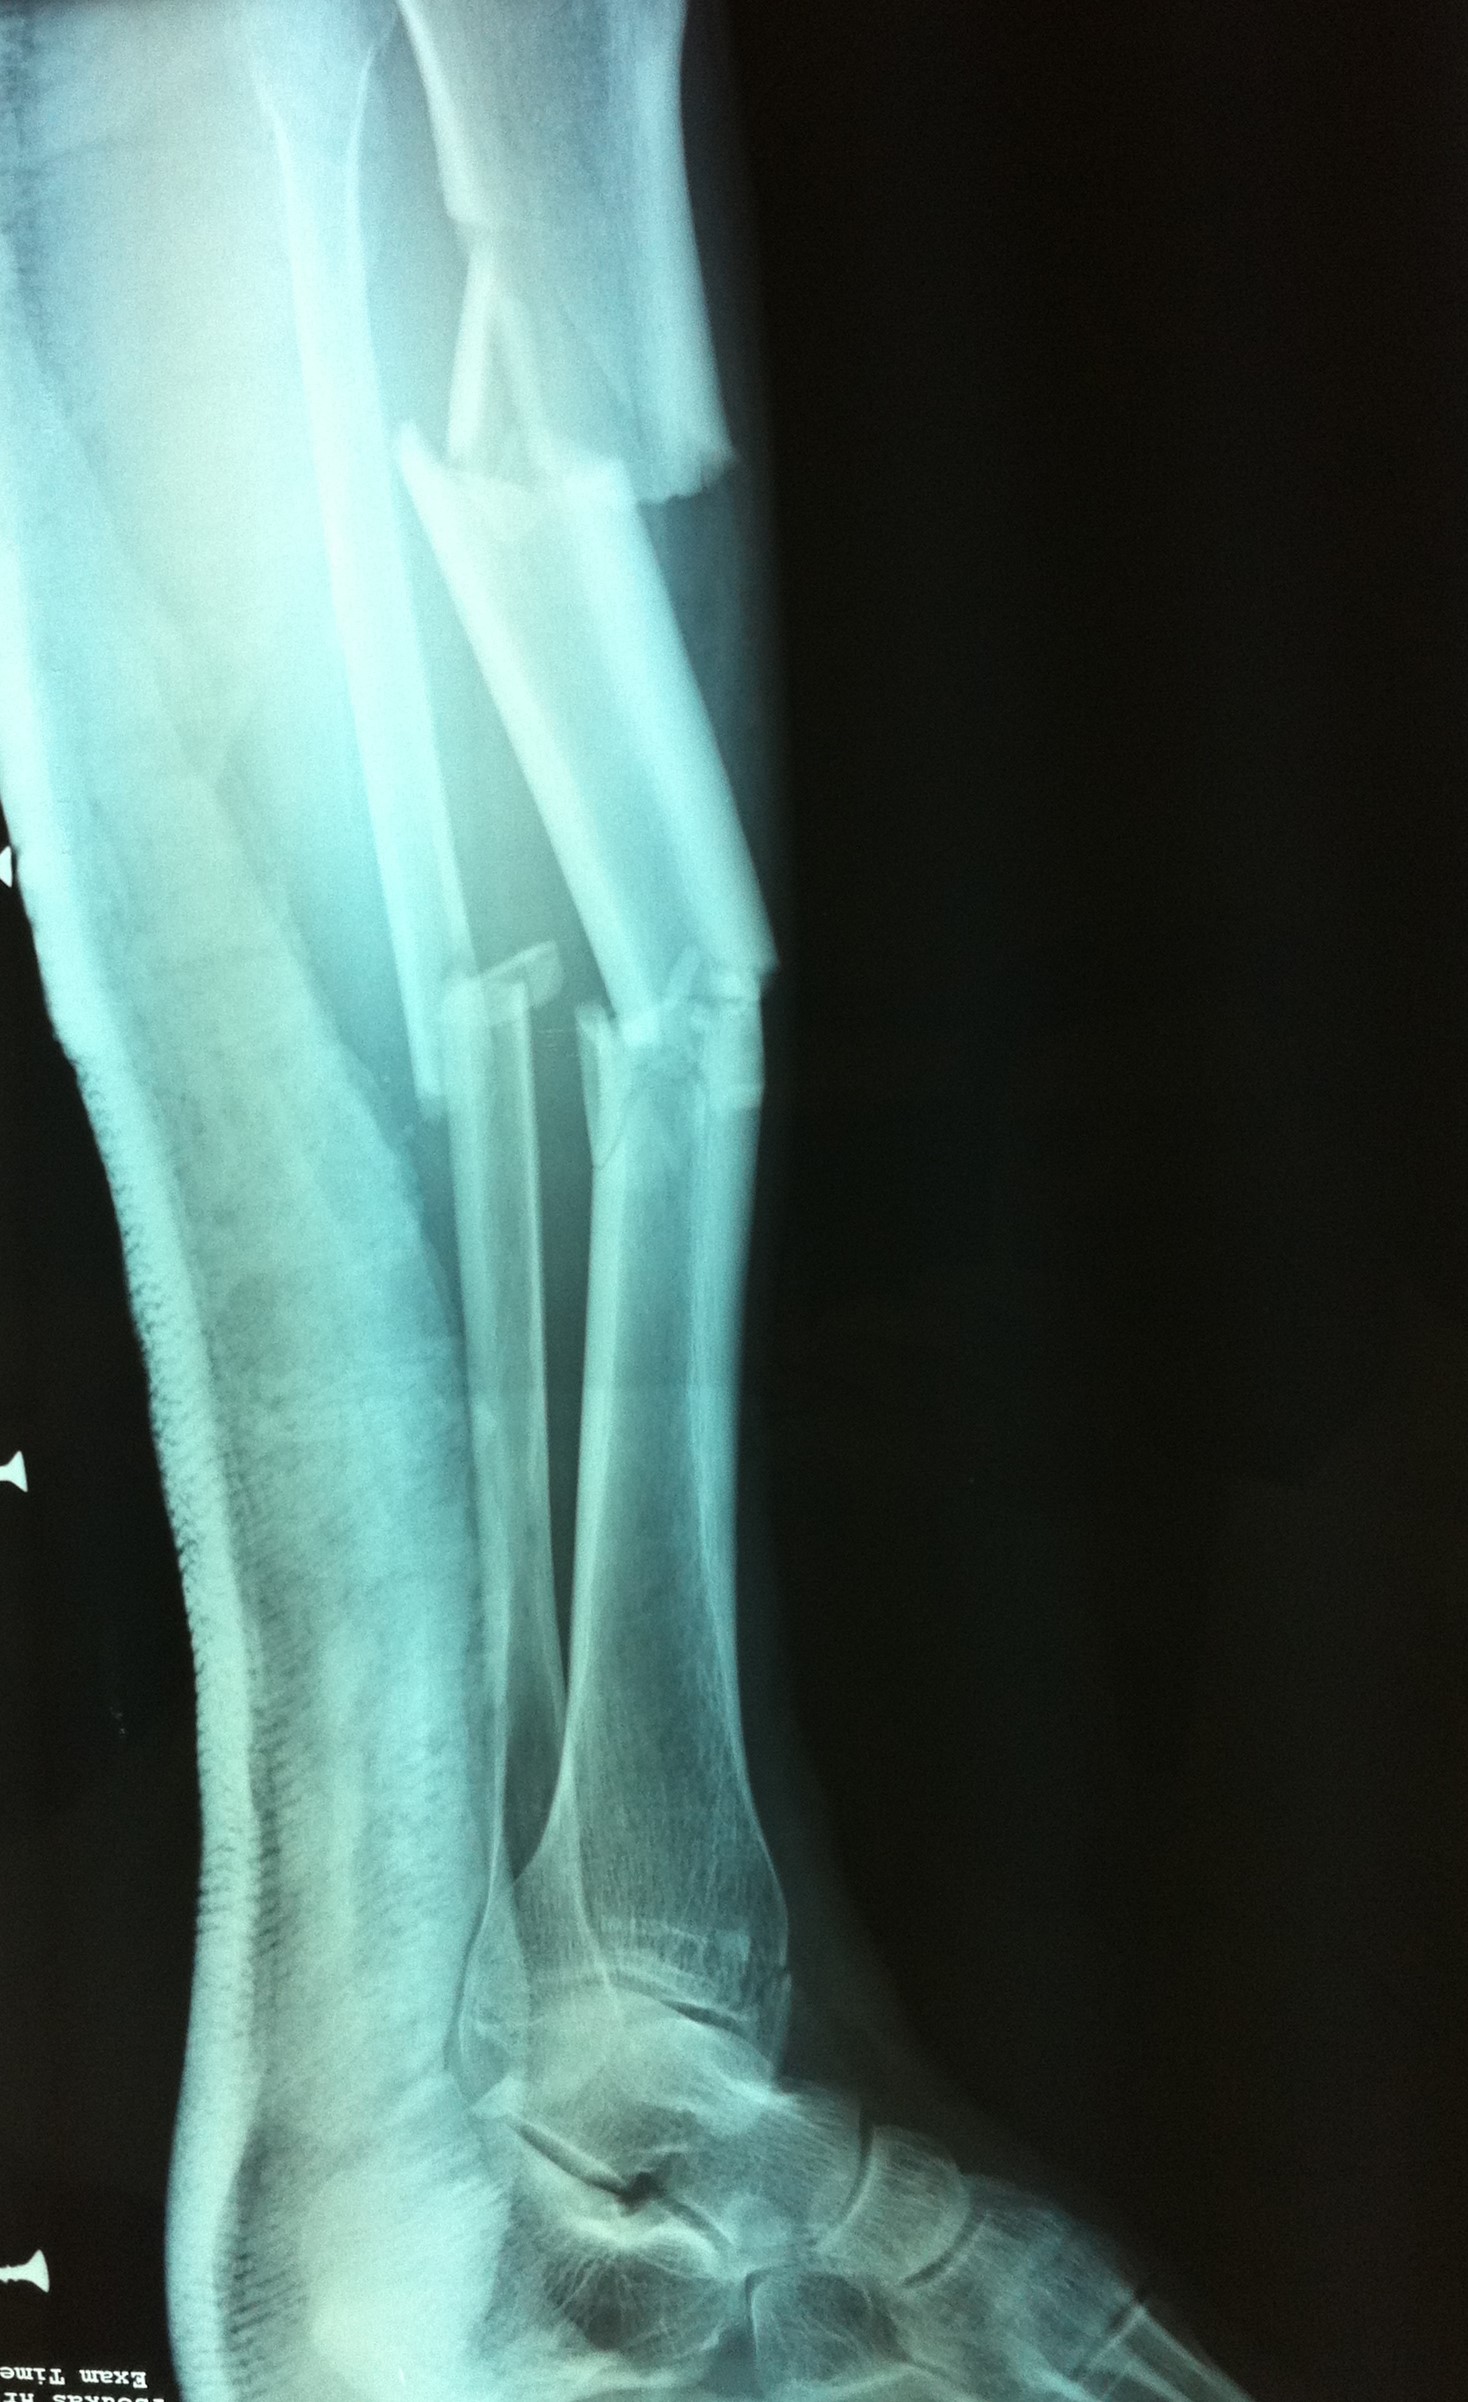

Ως κάταγμα κνήμης ορίζεται οποιοδήποτε διακοπή στην συνέχεια του οστού της κνήμης, είτε αυτή είναι ένα απλό ράγισμα (ρωγμώδες κάταγμα), είτε αυτή είναι μια εκτεταμένη συντριβή (συντριπτικό κάταγμα). Το κάταγμα κνήμης είναι ένα από τα συχνότερα κατάγματα. Πολλές φορές συνοδεύεται από κάταγμα της περόνης.

Η διάγνωση του κατάγματος κνήμης πραγματοποιείται μετά από μια επίσκεψη σε έναν έμπειρο ορθοπαιδικό. Σε πρώτο στάδιο η λήψη ενός λεπτομερούς ιστορικού και η κλινική εξέταση του ασθενούς είναι απαραίτητα για την διάγνωση. Στη συνέχεια, ο ασθενής υποβάλλεται σε απεικονιστικό έλεγχο με απλές ακτινογραφίες και σε κάποιες περιπτώσεις με αξονική ή/και μαγνητική τομογραφία. Οι απεικονιστικές εξετάσεις δίνουν σημαντικές πληροφορίες για τον τύπο του κατάγματος, που είναι απαραίτητες για τον καθορισμό της μετέπειτα θεραπείας.

Από την άλλη, η χειρουργική μέθοδος που θα επιλεχθεί εξαρτάται από τον τύπο του κατάγματος, τις λοιπές συνοδές κακώσεις και την εμπειρία του χειρουργού. Ένα κάταγμα κνήμης μπορεί να αποκατασταθεί με τοποθέτηση ενδομυελικού ήλου, με ανοικτή ανάταξη και εσωτερική οστεοσύνθεση με πλάκες και βίδες ή με εξωτερική οστεοσύνθεση.